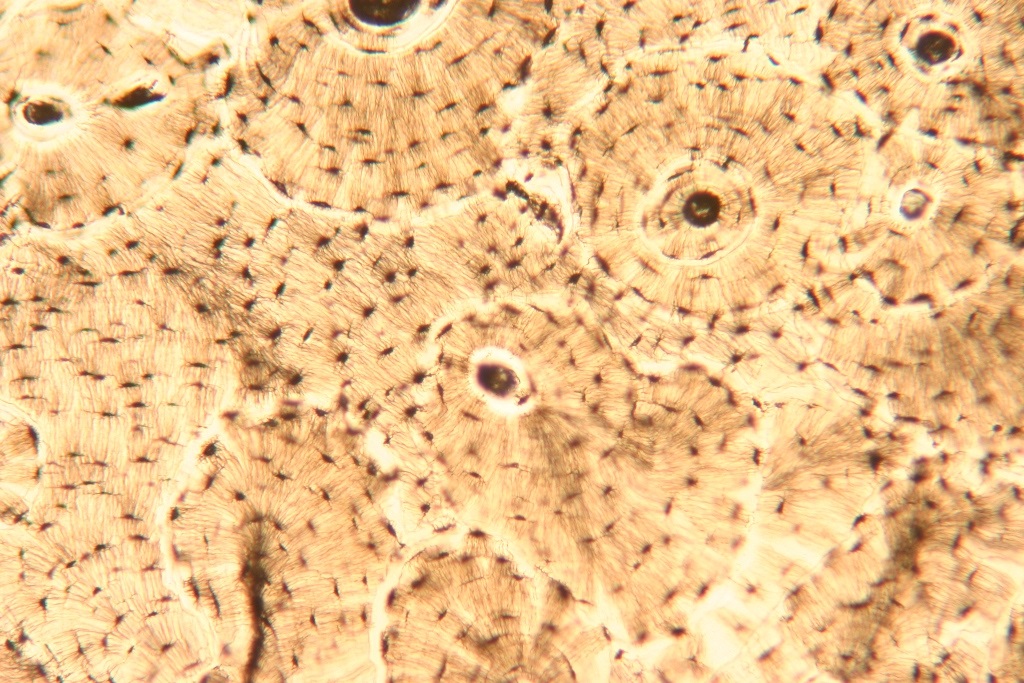

Структура грубоволокнистой костной ткани: наглядные примеры